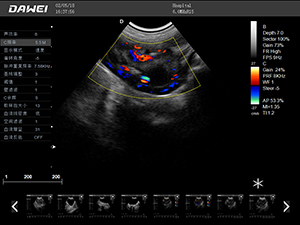

F5-VET彩色多普勒動物超聲診斷儀

F5-VET是一款性能可靠的獸用全數字彩色多普勒超聲診斷系統,基于Windows平臺 配置固態盤快速啟動 穩定可靠,融合了全面豐富的臨床應用,結合優異的人機工程學設計,推動了臨床診斷新趨勢。

·探頭接口:≥4個 可配備凸陣、微凸陣、線陣、相控陣、經直腸等各類獸用專用探頭,并配有犬、貓、馬等動物的專用測量軟件,是一款應用全面的獸用彩超。